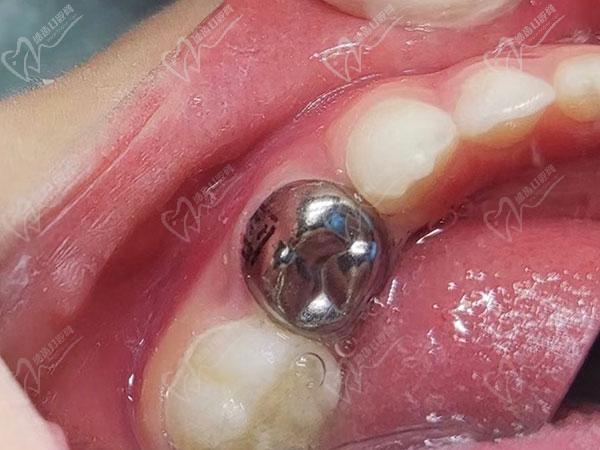

以下2种预成冠图片:

金属预成冠:

金属预成冠

金属预成冠通常会用于后牙,贴合的包裹后牙并保护牙齿,加强牙齿强度,保护恒压和乳牙能够正常替换。